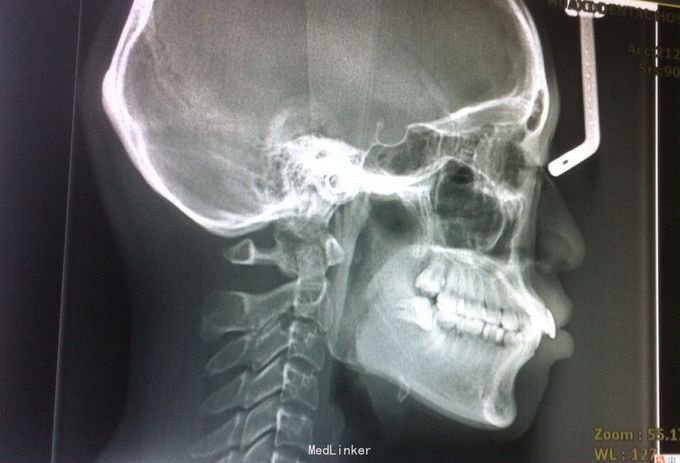

恒牙期 左侧磨牙中性关系,右侧远中关系 前牙三度深覆合 上合牙列中度拥挤,下颌重度拥挤 下颌中线偏右 关节有弹响

安氏二类,牙列拥挤 拔牙矫治,拔除14、24、34、44,强支抗,排齐整平上下牙列,矫治后磨牙中性关系,前牙覆合覆盖正常,面型略改善

1、治疗中可能需植入微种植体内收前牙 2、18、28、38、48存在,必要时建议拔除 3、正畸治疗后面型可能仍略突